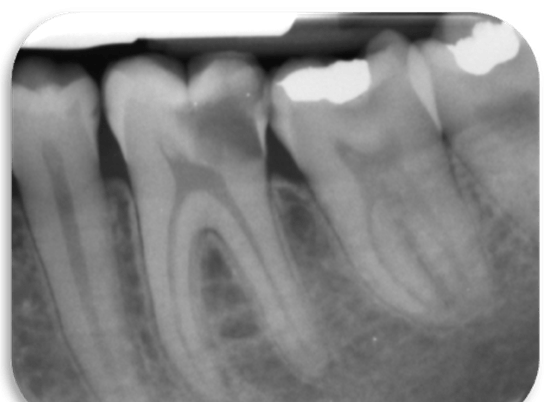

The standard treatment recommended for permanent teeth that are restorable but have irreversible pulpitis, is root canal therapy. Emerging evidence from randomized controlled trials suggest that, when the apical tissues are normal, pulpotomy with tricalcium silicate-based cements could be a successful and more economical intervention. A Quick Poll sought to learn more about these issues to guide further research on endodontics. A total of 416 practitioners answered the poll. The results revealed that:

- Approximately half of the practitioners used pulpotomy as part of their practice (55%); and 20% included pulpotomy as one of the most common clinical management strategies for irreversible pulpitis with normal apical tissues.

- Pulpotomy with tricalcium silicate-based cements such as MTA, Biodentine® and EndoSequence Root Repair Material® is a treatment option being employed by 19.5% of the practitioners surveyed.